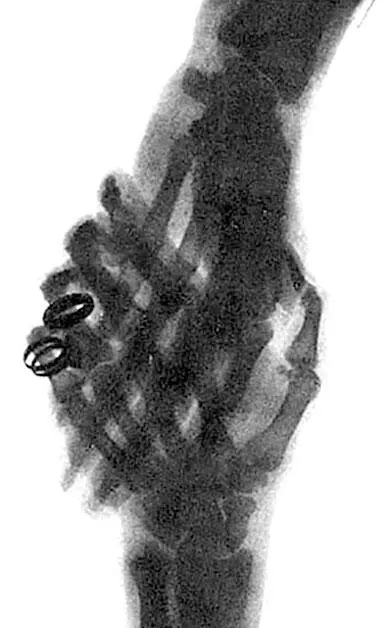

Рукопожатие рентгеновский снимок После этого Рентген проделал еще один опыт - фото 36

Рукопожатие (рентгеновский снимок)

После этого Рентген проделал еще один опыт, свой самый замечательный опыт.

Стеклянный баллон с разреженным воздухом он поставил под стол. На стол он положил руку, а на руку – фотографическую пластинку в деревянной кассете. Потом включил ток.

Когда фотографическая пластинка была проявлена, на ней оказалось отчетливое, резкое изображение костей руки. Икс-лучи прошли через кожу, через мускулы, но не в силах были пройти через кости. Тень костей запечатлелась на фотографической пластинке.

Так Рентгену удалось сделать то, чего никто еще до него не делал, – сфотографировать свои собственные кости.